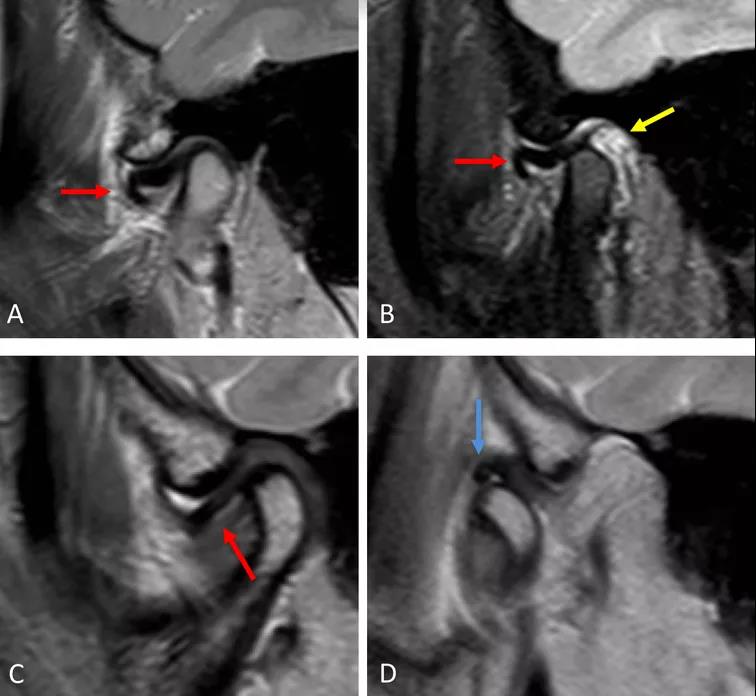

病例一:斜矢狀平面上的質子密度加權圖像(PDWI)

A圖示:閉口位時,顯示關節盤前移位明顯,雙凹形態消失。注意前帶的下移位(紅色箭頭)。

B圖示:張口位時,顯示關節盤移位(紅色箭頭),關節積液(黃色箭頭)。病例2:斜矢狀平面上的質子密度加權圖像(PDWI)

A圖示:閉口位時,顯示下頜骨髁突前上側面硬化,前方扁平的椎間盤移位(紅色箭頭)。